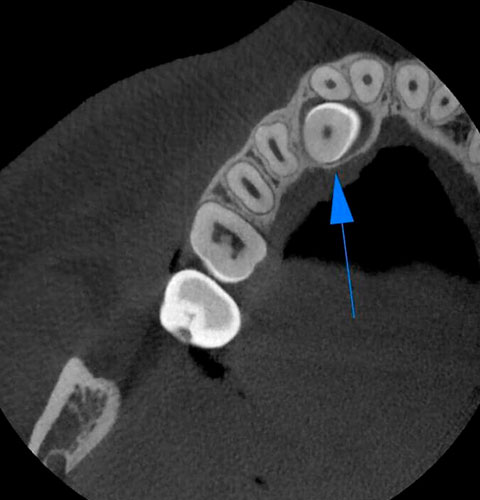

Veja exemplos de diagnósticos de imagem